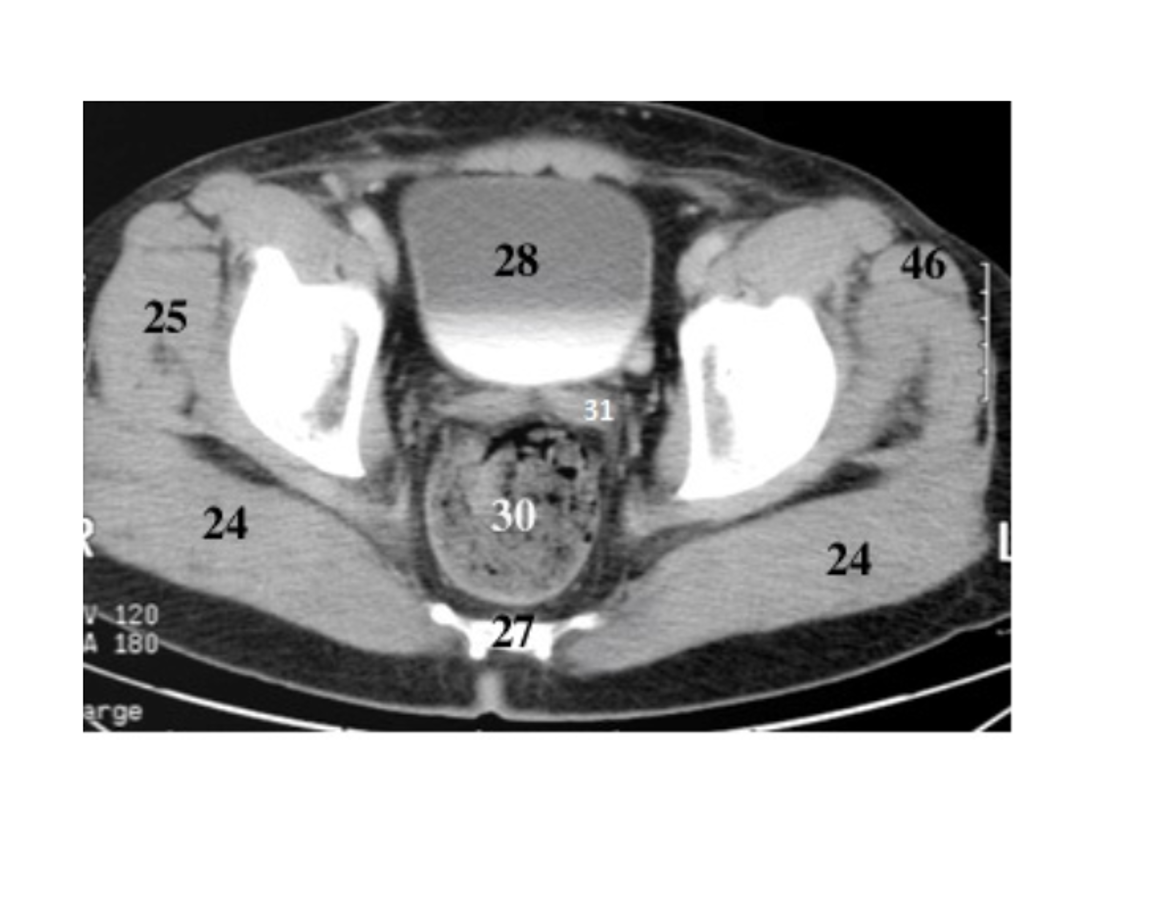

29

pubis

30

ishium

31

seminal vesicles

28

bladder

pubic symphysis